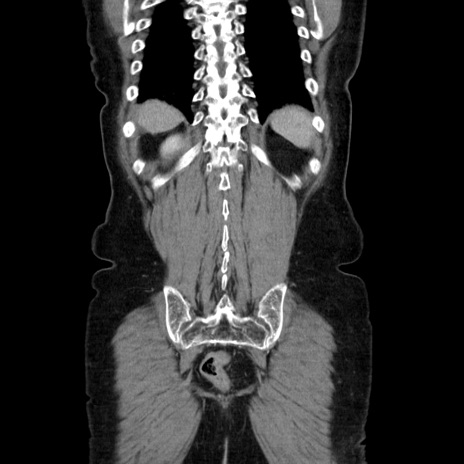

症例5(冠状断像)

【症例】70歳代女性

【主訴】お腹が張る

【現病歴】1週間くらい前から腹部膨満の自覚あり。昨日夜から増悪したため、本日救急外来受診。

【身体所見】意識清明、BT 36.5℃、BP 165/106mmHg、HR 80bpm、SpO2 98%、腹部:膨満、軟、自発痛・圧痛なし、触診にて不快感あり、腸蠕動音:減弱

【データ】WBC 12600、CRP 1.04